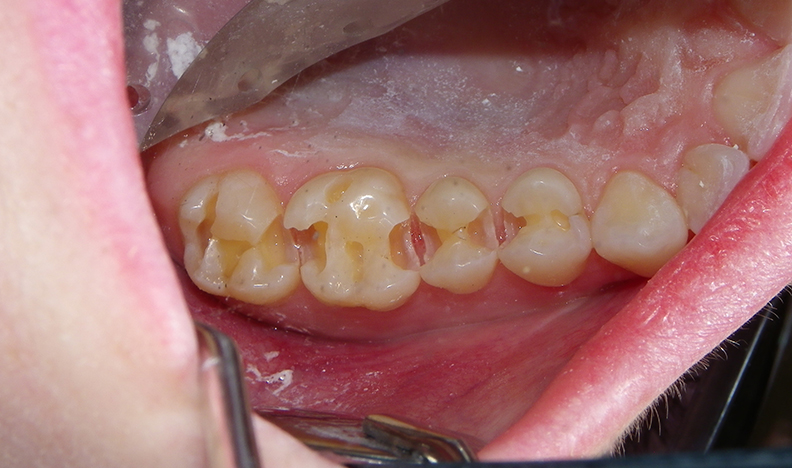

After educating the patient on the decay risks of this behaviour, oral hygiene instruction and a recommendation for a daily fluoride rinse, she can now take action to prevent any new cavities from developing for the rest of her life. There were many areas of decay between other teeth that we elected not to fill due to their small size, and hopefully they remain arrested / remineralized! (Aluminum oxide Air abrasion via PrepStart, 32% Phosphoric acid etch with Benzalkonium Chloride and AllBond Universal adhesive from Curion, Esthet-X Flowable A2 liner from Dentsply, Simplishade Medium resin core from Kerr).